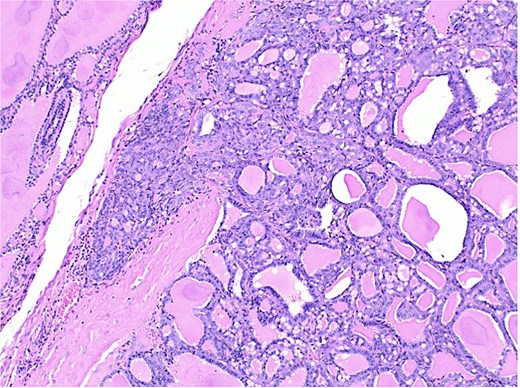

Sections of the left thyroid lobe and isthmus showing follicular neoplasia. A papillary carcinoma is visible in the lower part of the first section.

The final pathological report revealed a 1.4 cm classic papillary carcinoma in the isthmus, with extrathyroidal extension, without vascular, lymphatic, or perineural invasion, and with clear margins. In the left lobe, a minimally invasive follicular carcinoma of 3.5 cm was diagnosed, with capsular and limited vascular invasion (less than four vessels), without lymphatic or perineural invasion, and with clear margins (Figs 2–4).